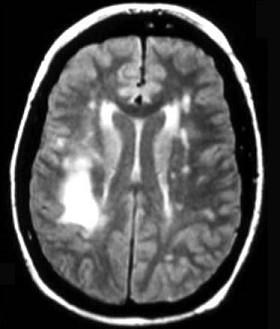

问题 根据MRI表现考虑为何种疾病是 ( )

选项 A、亚急性硬化性全脑炎 B、进行性风疹全脑炎 C、皮质—纹状体—脊髓变性 D、进行性多灶性白质脑病 E、羊瘙痒病 一、单项选择题

答案 D